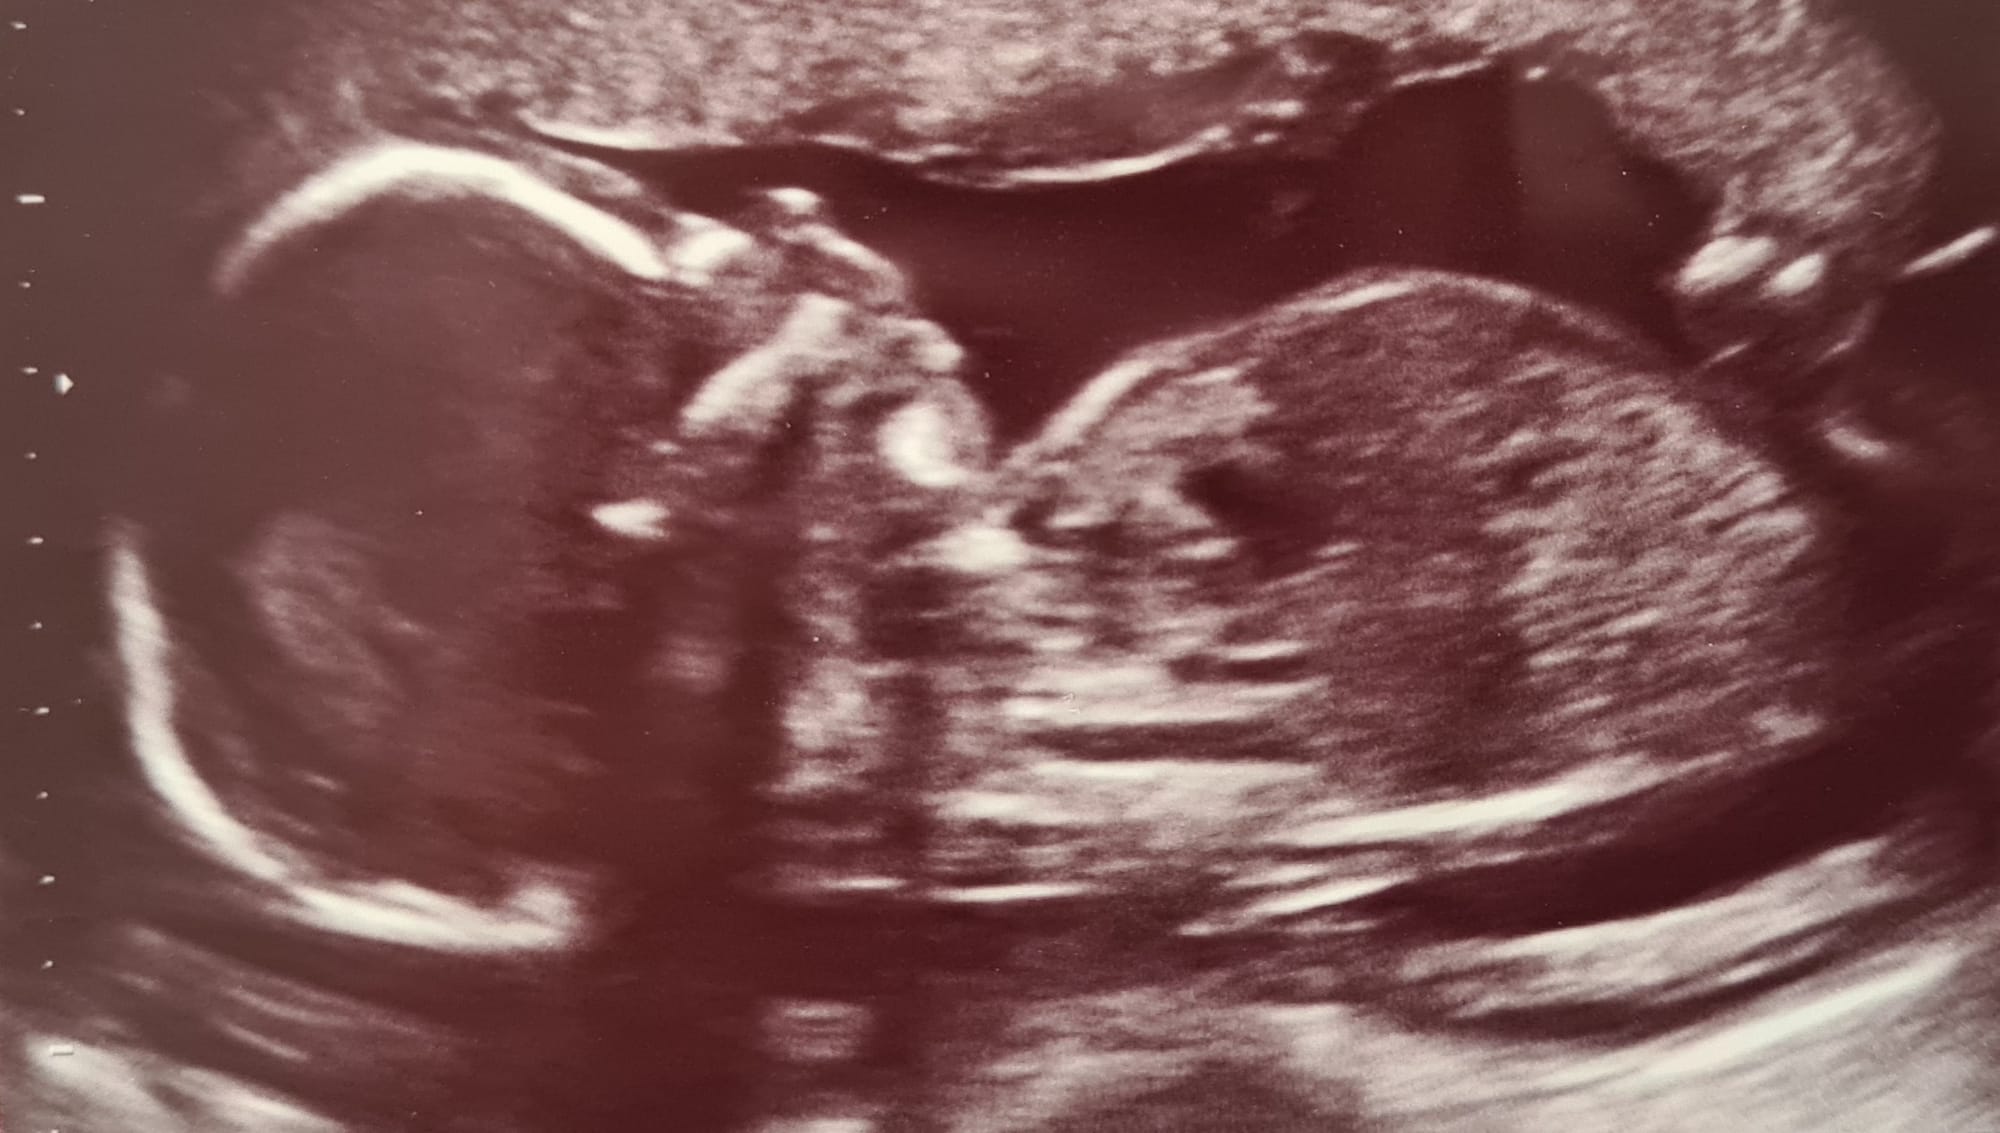

When I heard the diagnosis for the first time, I felt lost. As I slowly began to comprehend the future we would face and mourned the life I had envisioned, I found myself with more questions than answers at every turn. Every search on Google needed to be taken with a (heavy) pinch of salt. So, I approached it as I would any other assignment, much like many others I had during my decade as a journalist: I arranged meetings with doctors who could provide the best answers and scheduled a visit to the wards at the Children's Cardiac Center in Bratislava, Slovakia, the institution we had chosen to care for our baby.

As I gathered more information on Congenital Heart Defects (CHD) and specifically, what it meant to have a single ventricle heart, I realized what I wanted to know most was how they could fix it.

We wanted to understand everything about our daughter's heart, her diagnosis, the procedures we could expect, the options we might have, and the potential outcomes. I needed to hear about the worst-case scenario as well as the likelihood of complications. We wanted to be able to make informed decisions when needed.